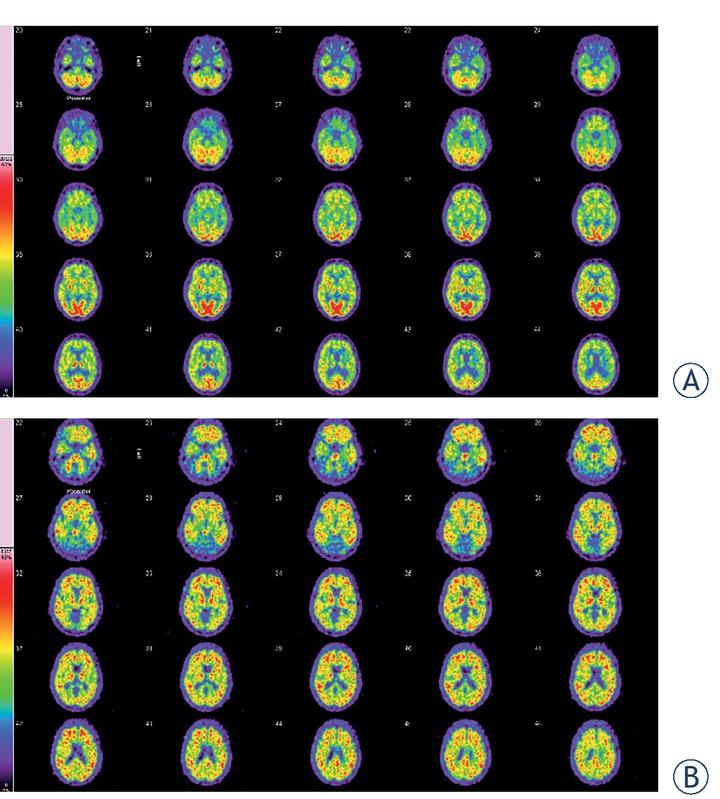

Figures 1 and 2 demonstrate FDG PET and amyloid positive PET images of patients with the clinical suspected diagnosis of AD.

FDG and amyloid brain PET/CT of a 70-year-old woman. (A) 2-[18F] fluoro2-deoxy-d-glucose (FDG) brain PET/CT of a 70-year-old woman, who presented with a history of cognitive decline (mini mental state examination [MMSE] = 15/30). The glucose metabolism in the cerebral cortex is inhomogenous and moderately attenuated. In the cerebellum, normal glucose metabolism was demonstrated. This FDG brain PET study does not show the typical picture of abnormal glucose metabolism that occurs in Alzheimer´s disease (AD), but temporomesial and temporolateral some decreased tracer uptake can be observed. Additionally the images are compatible with pronounced microvascular changes. (B) Amyloid PET images demonstrate pathologically increased tracer accumulation in the entire brain, more pronounced in the frontal and temporal cortical areas. This is compatible with the diagnosis of AD.